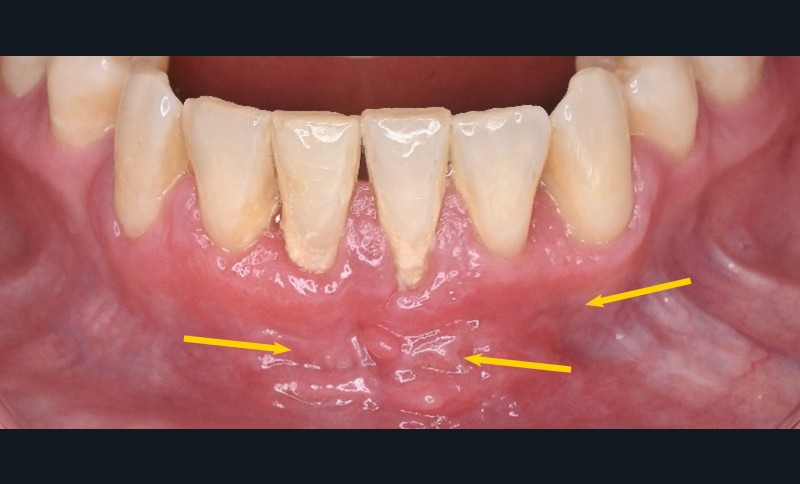

L’examen des muqueuses révèle également, au niveau de la muqueuse vestibulaire antérieure mandibulaire, la présence de fissures linéaires et d’excroissances muqueuses (pseudopolypes), fermes, d’aspect érythémateux et inflammatoire, douloureuses à la palpation (fig. 1).